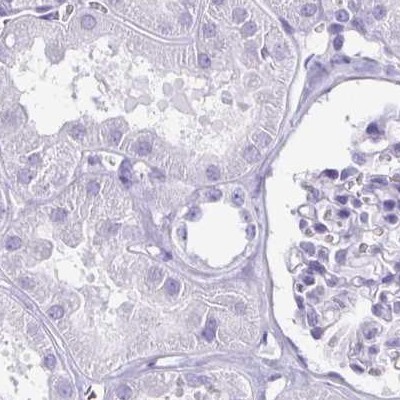

Immunohistochemistry analysis in human fallopian tube and colon tissues using Anti-ENKUR antibody. Corresponding ENKUR RNA-seq data are presented for the same tissues.